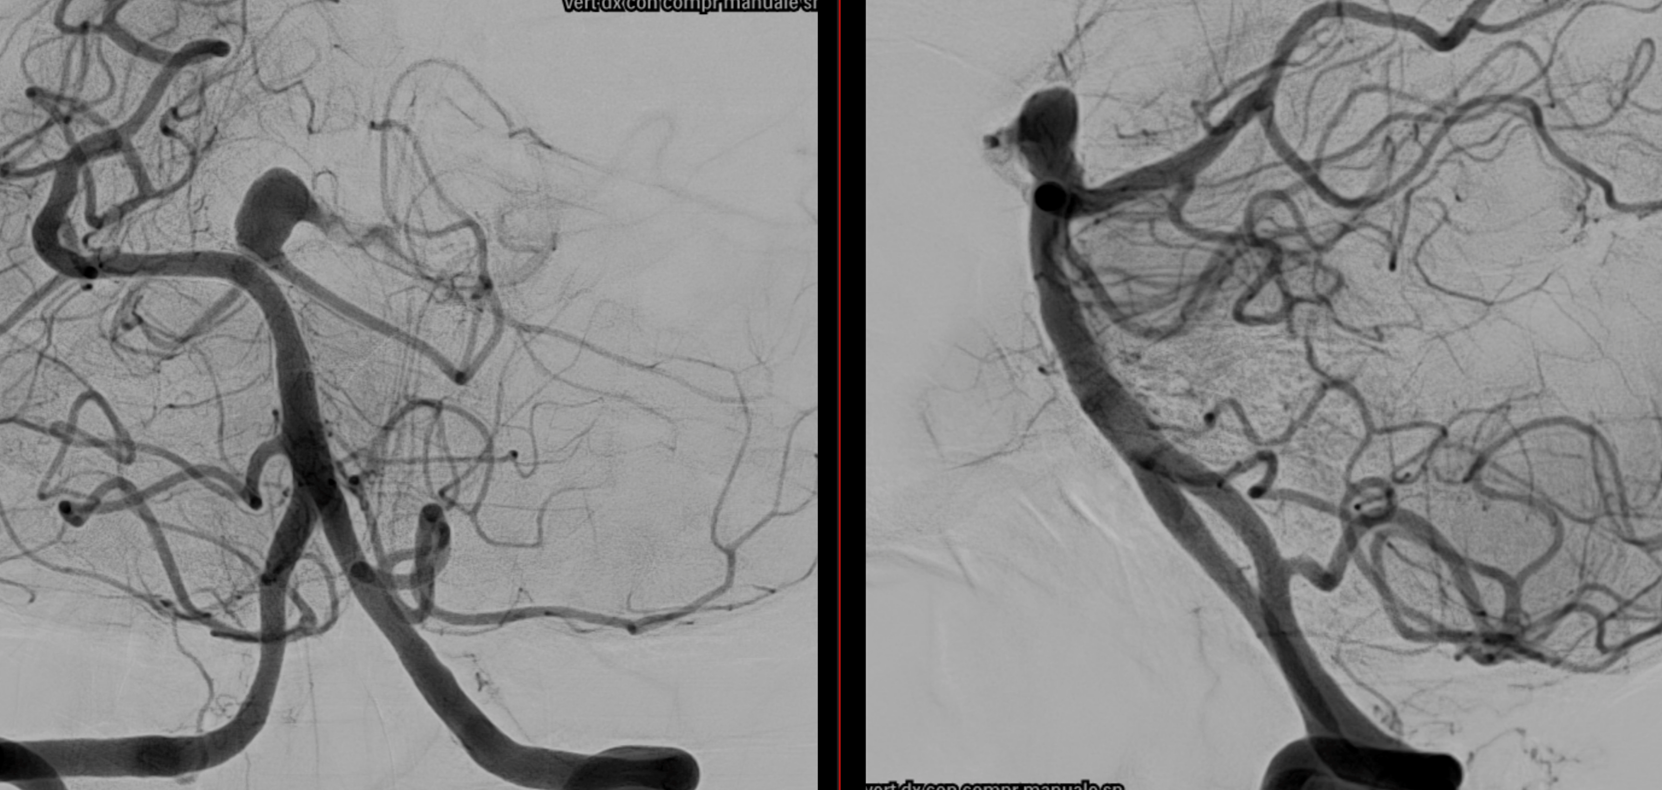

Very Important Case of Aggressive Basilar Bifurcation Aneurysm

Unruptured basilar tip aneurysm treated in 2010 with PED between right P1 and basilar.

Make sure you don’t judge — we know much more about how these behave now than in 2010 — and many people today still coil these with laser-cut stents and mess up options for the guaranteed recurrence

The aneurysm was kept open by the left (contralateral) PCom — again, we know this much better now than in 2010. And its very important.

13 year later. The aneurysm was mostly thrombosed and was growing, becoming symptomatic. The good old analog Philips workhorse is gone… Welcome to the digital world or Azurion

With manual compression of the left carotid — look how important manual compression or Balloon Test Occlusion can be

Left ICA — the preferential supply to bilateral SCAs is clearly seen

3D reconstructions of the left ICA (3D 5 seconds acquisition, 22 cm FOV, manual injection of pure contrast – 300 mg/ml – with a 20 ml syringe, no secondary reconstructions). Both the SCAs are injected by the PCom and the right SCA origin is shaped by the PED in right P1. Now in left P2 there is a fusiform dilatation, not present before